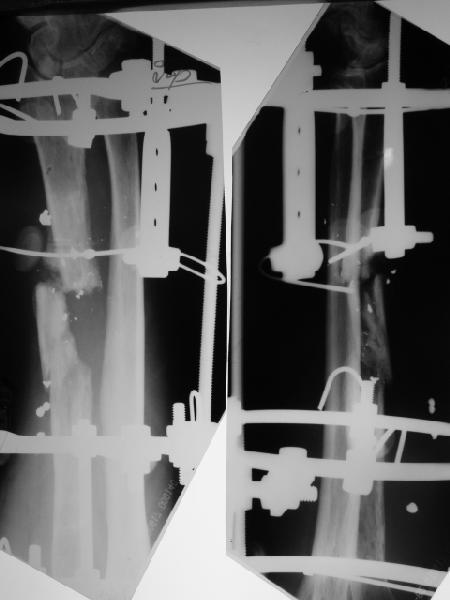

Re: Огнестрельный перелом луча

Пока мы наложили аппарат для восстановления оси и длины лучевой кости. Снимок прлагаю.